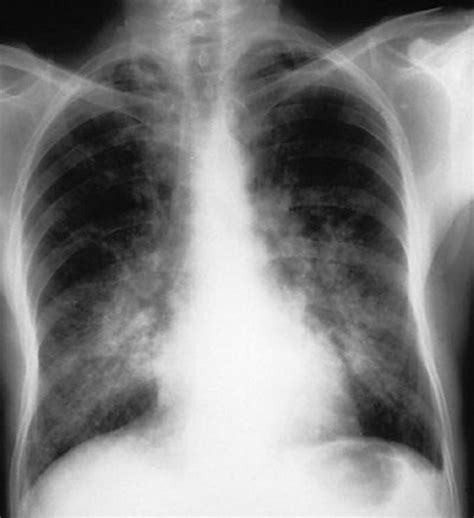

• Imaging Tests: Chest X-rays and CT scans can help visualize the lungs and identify areas of bleeding.

• diffuse alveolar hemorrhage radiology

• diffuse alveolar hemorrhage cxr